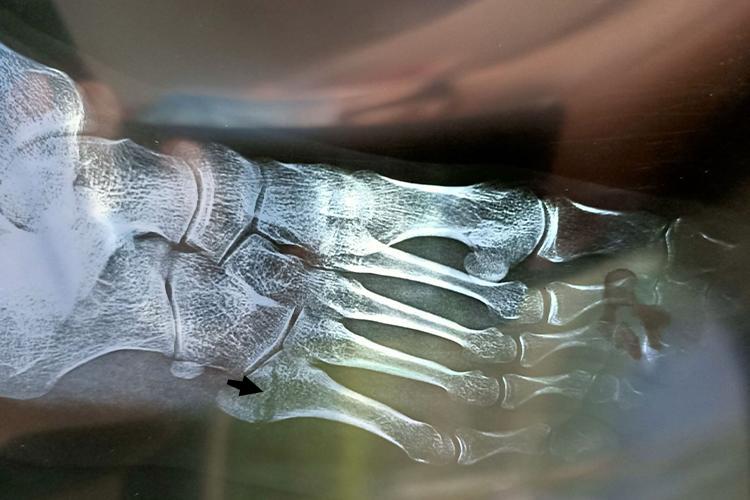

骨折泡脚,作为一种辅助的康复手段,在一定程度上可以对骨折愈合产生积极的影响,但需注意其并非直接促进骨折愈合的主要方法,而是通过改善局部血液循环、缓解肿胀与疼痛等间接作用来辅助骨折的康复过程。

- 需要明确的是,骨折的愈合主要依赖于骨折部位的稳定固定、充足的营养供应以及机体自身的修复能力。

- 这样一来,骨折部位的环境得到了改善,有利于骨折断端的修复和骨痂的形成。